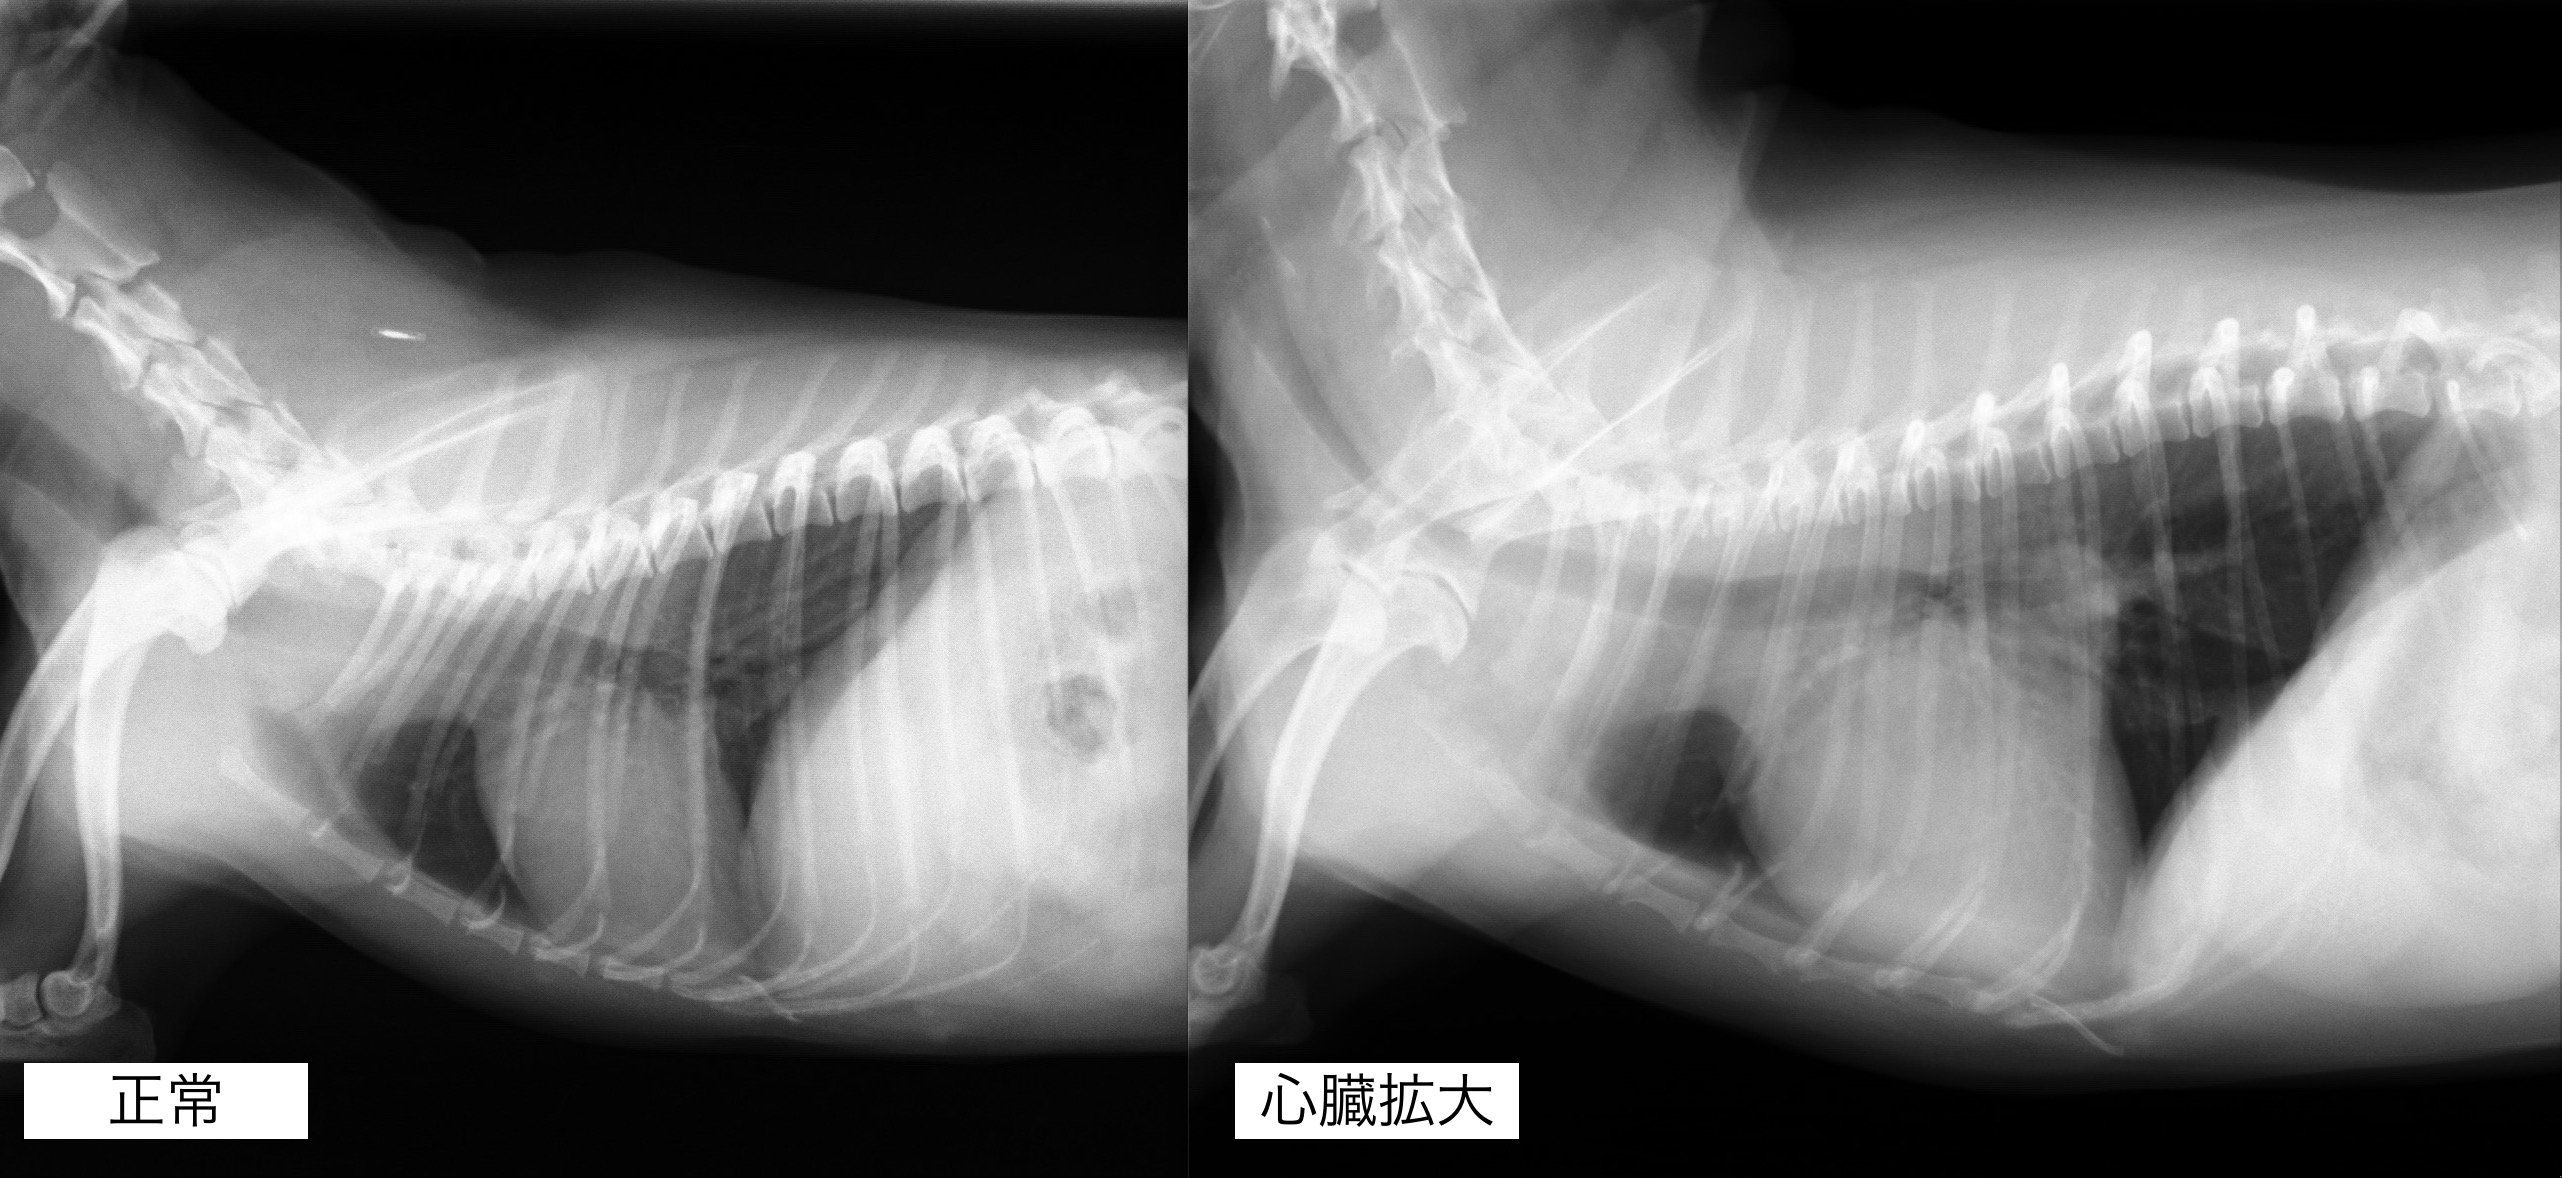

聴診検査にて心雑音が観察され、レントゲンん検査では心臓の明らかな拡大が認められました。

内服開始1ヶ月後のレントゲン検査です。

心臓の拡大はやや改善しており、咳の頻度も減っているとのことでした。